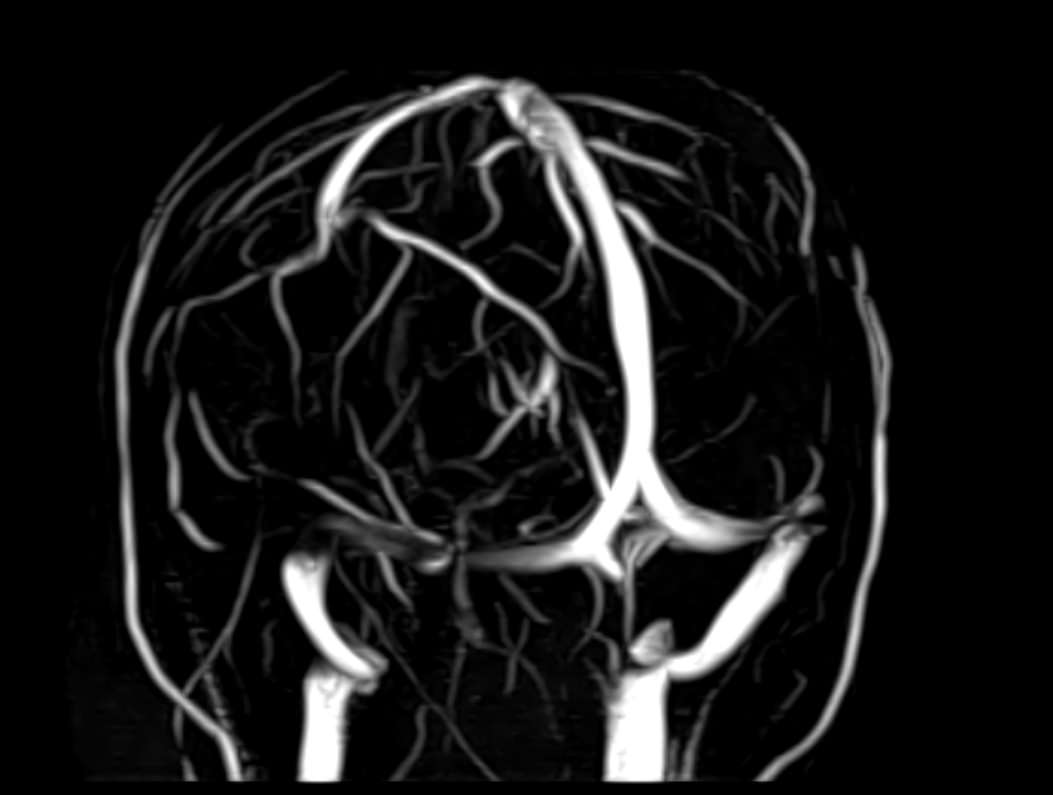

Для диагностики поражения черепно-мозговых нервов, а также оценки состояния окружающих их тканей и визуализации сосудистой сети головного мозга в клинике «Доступная медицина» проводится комплексное обследование МРТ головного мозга + Мр-ангиография головного мозга + МР-венография головного мозга + черепно-мозговые нервы. Данное обследование включает в себя несколько протоколов: стандартный – для оценки состояния всех структур головного мозга и дополнительные – для изучения очагов поражения черепных нервов и визуализации всей сосудистой системы головного мозга.

Исследования выполняются на современном высокопольном томографе экспертного класса TOSHIBA VANTAGE TITAN 1,5 Тесла, который использует разные режимы сканирования с толщиной среза от 1мм в различных плоскостях с последующей цифровой обработкой полученных данных для создания трехмерных изображений. МР-ангиография отображает состояние артериальной системы кровоснабжения головного мозга. МР-венография головного мозга позволяет детально изучить особенности венозного русла головного мозга.

Компьютерная программа обрабатывает данные, полученные при сканировании, и формирует объемные изображения как самого мозга, так и сосудистой системы в отдельности без прилегающих тканей. Методики применяются одновременно и взаимодополняют друг друга.